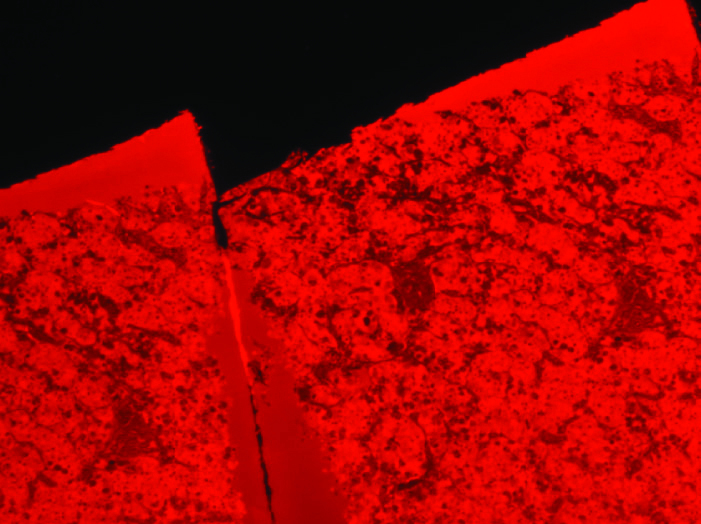

Human anterior pituitary, FIRM, rhodamine channel. Note that the fluorophore illuminates the LR White resin, providing an image of tissue structure primarily in negative relief. Bar, 100µm. All subsequent FIRM images are shown in monochrome.

Human anterior pituitary, formalin-fixed autopsy specimen, comparison of H&E paraffin section (left) with FIRM (right). 20x dry objective used for both. Scale bar, 20µm.